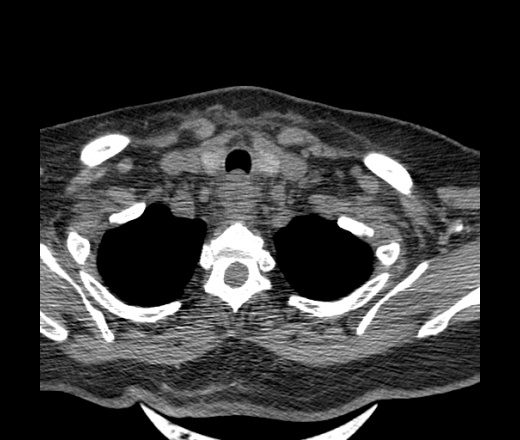

Женщина поступила в х/о спустя 4 дня после того как при употреблении карася подавилась костью.

Наличие газа в средостении на протяжении тел С2-С6 (медиастинальна эмфизема); рыбная кость на уровне тела С6.

При всем уважении, но говорить о медиастинальной эмфиземе, оценивая мягкие ткани шеи, как-то слишком резко. На мой взгляд, это ретрофарингеальное пространство.

Эвакуировали почти 100мл гноя. Но кость не смогли найти. Думаю что она даст дальнейшее ослоднение. Эндоскопически за черпалонадгортаной звязкой не смогли зайти в пищевод, все мягкие ткани отечные, просвет пищевода сдавлен. По всей видимости параэзофагеальная клетчака тоже задействована. Эмпиема, если ее можно так назвать, незнаю как правильно дошла до уровня яремной вырезки. Чем закончиться напишу. Ждем медиастинита.

Флегмона заглоточного пространства шеи, только операция, флегмоны вскрывают. Риск медиастинита.

Согласен с Вами; конечно, наличие газа в клетчатке ретрофарингеального пространства (затмение с опечаткой..). К сожалению, процесс "продвигается" к медиастиниту. Но почему никто, не отмечает наличие рыб. кости; или это для Всех очевидно?

Так вы уже отметили. Хотя ориентировал бы не скелетотопически, а на перстнечерпаловидный сустав.

Кость то мы сразу выявили, размеры где то 17*2мм, но ее так и не получается найти в этой каше